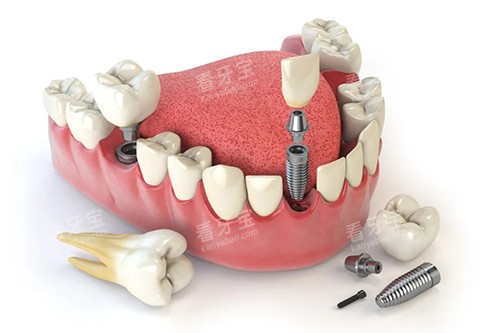

种植牙技术方面,美奥口腔采用的即刻种植、小创口种植等技术,能够大大缩短治疗周期,提高种植可行性。